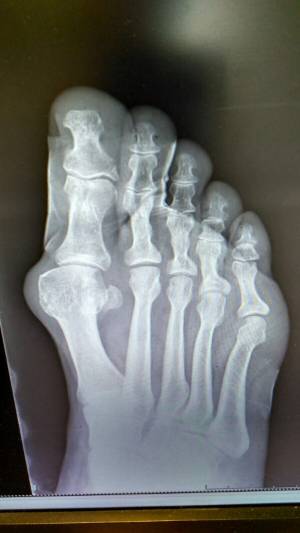

Estas deformidades son los llamados Hallux Valgus o popularmente conocidas como juanetes, que son deformidades que se generan en la parte externa del dedo gordo del pie cuando éste se desvía y comienza a apuntar hacia el segundo dedo. Es una afección que se vuelve dolorosa según evoluciona, y en cuya aparición influyen factores genéticos y posturales. Se puede prevenir utilizando calzados de horma ancha, pero cuando la afección es grave, finalmente la cirugía es la solución.

"Bajo anestesia local y una suave sedación se pueden realizar todas las correcciones que se requieran durante la cirugía. Hoy en día los equipos modernos como el fluroscan, nos proporcionan imágenes directas del pie sin tener que abrirlo y a través de pequeñas incisiones estratégicamente localizadas con un micro instrumental, vamos corrigiendo la deformidad utilizando un motor de revoluciones controladas con fresas especiales para quitar el sobre hueso; no colocamos ningún tornillo, ninguna aguja, ningún elemento de síntesis. El paciente sale caminando del quirófano por su propio pie con un zapato especial de suela de goma recta y velcro que utilizará durante un mes. A la semana de la intervención se retira el vendaje y los puntos de sutura, se coloca un vendaje de mantenimiento, de fácil colocación, que se cambia cada vez que el paciente lo demande por su higiene, reanudando una vida activa en forma progresiva, alternando con periodos de reposo", explica el Dr. Lipnizky.

Al mes de este procedimiento ambulatorio, se realiza un control aportando una radiografía y acorde a la evolución, se retira el zapato rígido para comenzar a calzarse uno convencional y se indica un plan de ejercicio de recuperación funcional.